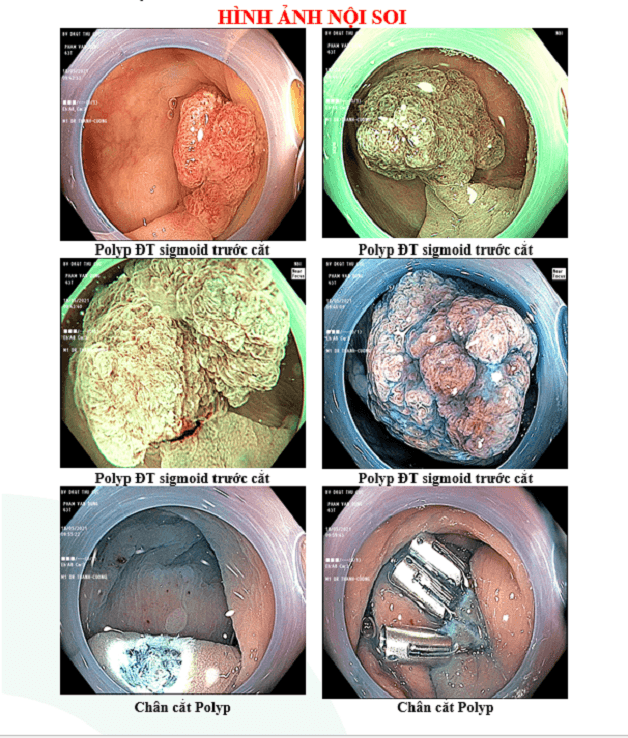

3. Một số hình ảnh thực tế từ một ca nội soi MCU tại Hệ thống Y tế Thu Cúc TCI

Cùng theo dõi một số hình ảnh thực tế từ một ca nội soi MCU:

Khối polyp đại trực tràng sau khi được cắt bỏ ngay ở lần thực hiện nội soi MCU duy nhất.

Hình ảnh kết quả nội soi MCU trước và sau cắt polyp đại trực tràng.